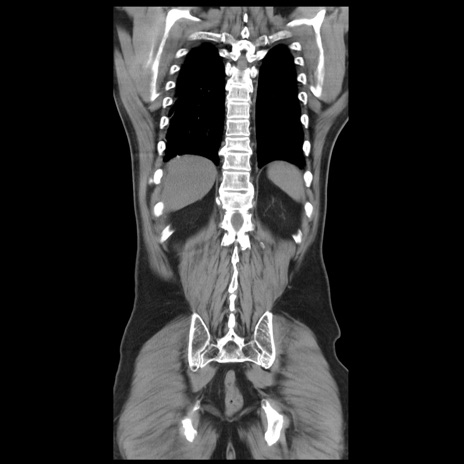

症例20(冠状断像)

【症例】 60歳代男性

【主訴】 腹部膨満、嘔吐

【現病歴】5日前頃より倦怠感を認め食事量減少し4日前の朝嘔吐、食事摂取困難となった。 3日前近医受診し点滴施行され整腸剤などを処方された。 当日他院を受診し、腹部膨満著明、炎症反応の上昇(CRP10.8、WBC11200)あり、紹介受診となる。

【身体所見】 意識JCS1 受け答えがはっきりしないBP 111/57mHg、 P 67bpm、、BT35.2°C、SpO2 97%(RA)、 腹部:膨隆、打診で鼓音あり、全体的に圧痛有り、腸蠕動音(-)、反跳痛ははっきりせず。

【データ】WBC 11400、CRP 14.20